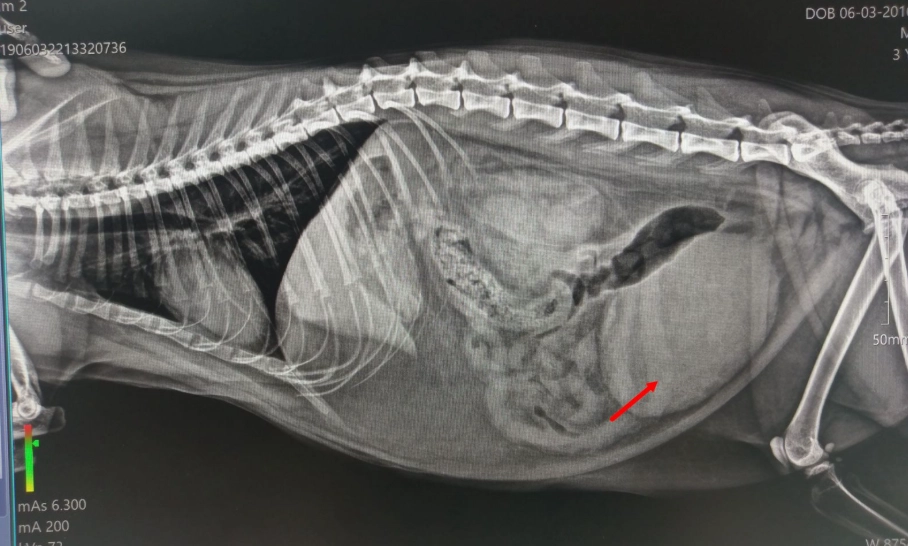

診斷膀胱結石通常需要影像學檢查。X光能顯示鈣化結石,但有些結石(如尿酸結石)在X光下不顯影,這時超音波就派上用場。尿液分析則可檢測pH值、結晶和感染。

手術不是首選,但在某些情況下不可或缺。例如,結石大於1公分、阻塞尿道、或引起反覆感染。手術方式包括膀胱切開術,透過腹部切口移除結石。

獸醫會根據X光、超音波和尿液分析來判斷。如果結石小於5毫米,且狗狗沒有阻塞症狀,可以先嘗試非手術方法。但若結石導致排尿困難、血尿或感染,手術可能是必要選項。